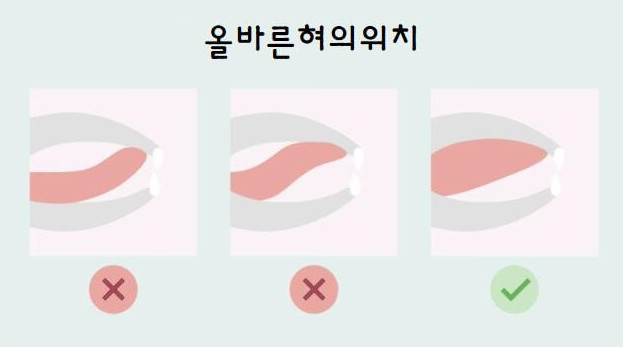

혀의 위치를 입천장에 놓음으로써 Airway 확보와 코로 숨을 쉴 수 있게끔 만들어 주는 건데요. 사실 입으로 숨을 쉬는 분들은 굉장히 힘든 운동입니다. (혀의 근육저하와 코로 숨쉬기 힘들기 때문이죠)

사진과 같이 올바른 혀의 위치이지만 의식 했을 때는 할 수 있으나 잠을 잘 때는 무의식중이기 때문에 쉽지가 않습니다.

혀의 위치를 입천장에 놓음으로써 Airway 확보와 코로 숨을 쉴 수 있게끔 만들어 주는 건데요. 사실 입으로 숨을 쉬는 분들은 굉장히 힘든 운동입니다. (혀의 근육저하와 코로 숨쉬기 힘들기 때문이죠)

사진과 같이 올바른 혀의 위치이지만 의식 했을 때는 할 수 있으나 잠을 잘 때는 무의식중이기 때문에 쉽지가 않습니다.